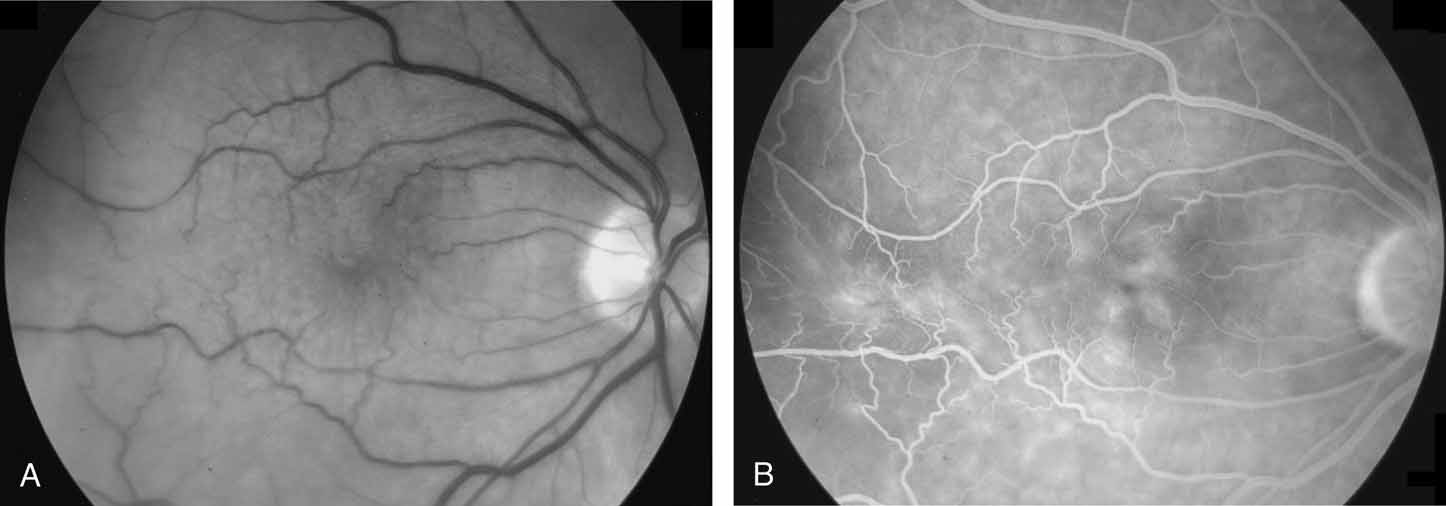

The clinical appearance is variable and may present as only a mild sheen or glint in the macular region that can best be seen with red-free or monochromatic green or blue light (Fig. 5). In more severe cases, there is increased vascular tortuosity and the perimacular vessels are seen to be pulled toward an epicenter, with striae and heterotopia of the macula. The superior and inferior arcuate vessels are also closer together and straighter than in an uninvolved eye. Other findings that may be present include small intraretinal hemorrhages, cystic changes in the macula, macular edema, and cotton-wool spots.110 Pseudoholes or macular cysts have been noted in up to 8% of idiopathic cases (Fig. 6).25,88 Thin membranes may be completely translucent, whereas thicker membranes are frequently opaque or pigmented and generally obscure details of the underlying fundus (Fig. 7).110–112 The thicker and occasionally pigmented membranes are often seen after retinal detachment surgery, severe inflammatory conditions, and trauma. An apparent posterior vitreous separation has been reported by most authors to exceed 75% in cases of idiopathic epiretinal membranes.84–88,93,104,105,113–117 It is sometimes difficult to accurately determine the vitreoretinal relationships preoperatively.

Fig. 6 A. Idiopathic epiretinal membrane with macular pseudohole in a 35-year-old woman. B. Postoperative appearance with disappearance of macular pseudohole and improvement in vision from 20/100 to 20/40. (Margherio RR: Epiretinal macular membranes. In Albert R, Jakobiec EA, eds. Principles and Practice of Ophthalmology, Vol. 2. Philadelphia: WB Saunders, 1993:919–925)

Clinical testing, in addition to visual acuity, most commonly involves fluorescein angiography and ocular coherence tomography. Fluorescein angiography can show retinal vascular tortuosity, straightening, and leakage, as well as cystoid macular edema (Fig. 8). OCT typically demonstrates retinal folding, increased macular thickness, cystoid macular edema, traction macular retinal detachment, and both lamellar or macular hole formation (Figs. 9, 10, and 11). Sine Amsler chart testing may help quantify metamorphopsia in eyes with macular distortion.118 Abnormal macular function has been shown using both focal and multifocal electroretinography.119,120

Fig. 8 A. Black and white photograph taken with a green 540-nm filter, showing dragging and distortion of the macular vessels. B. Fluorescein angiogram. Note distortion of macula and vessels, with associated vascular leakage and cystoid macular edema.